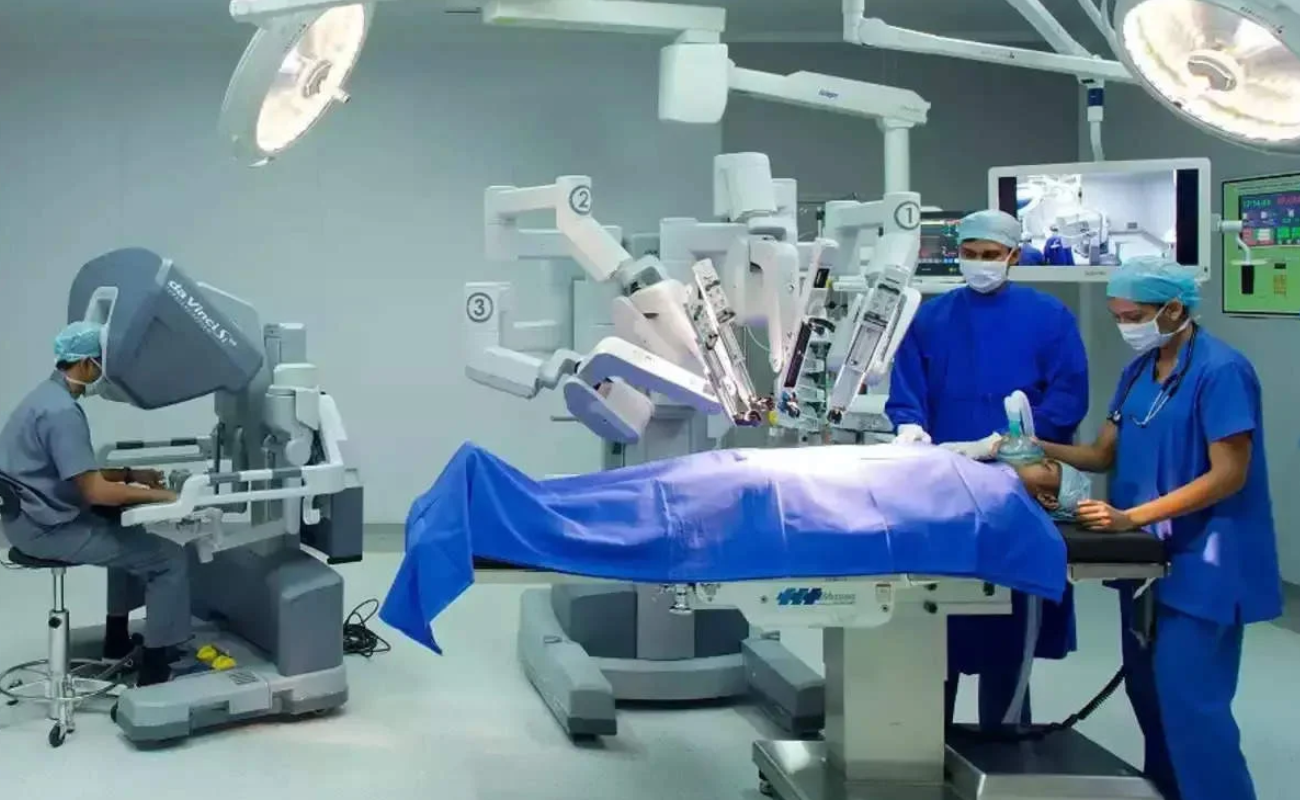

With state-of-the-art robotic joint replacement surgery offering greater accuracy, smaller incisions, and faster recovery times.

The Benefits of Robotic Knee Replacement Surgery

In recent years, medical technology advancements have brought about a revolution in the field of orthopedic surgery, particularly in the realm of knee replacements.

The Impact of Robotics on Knee Replacement: Revolutionizing Orthopedic Surgery

In recent years, orthopedic surgery has undergone a revolutionary transformation through the integration of robotics in knee replacement procedures.

Knee Replacement Surgery: A Comparison of Traditional and Robotic Techniques

When it comes to addressing debilitating knee pain and restoring mobility, knee replacement surgery has been a transformative solution for many individuals.

Transforming Healthcare: Robotic Hip-Replacement Surgery Trends in 2024

In 2024, the healthcare landscape in India is undergoing a remarkable transformation, particularly in the field of orthopedic surgery. Robotic hip-replacement surgery, a revolutionary advancement,

Robotic Surgery: The Future of Healthcare in Chennai

Robotic surgery is revolutionizing healthcare, particularly in Chennai, where advanced medical techniques are becoming increasingly accessible

Chennai Apollo hospital performs 370 robot-assisted orthopedic procedures in 10 months

A robotic knee replacement is just like a traditional knee replacement. The surgeon removes damaged tissue and replaces it with an artificial joint.

Robotic Surgery in Chennai: A Guide for Patients and Caregivers

Robotic surgery is transforming modern healthcare, offering precision, minimally invasive techniques, and faster recovery for patients. As one of the most significant advancements in surgical technology,

What Are the Benefits of Robotic Surgery and Why Do People Choose It?

A surgeon’s hands have been augmented by a machine capable of millimeter-perfect precision. Robotic surgery, a groundbreaking medical innovation that is redefining surgical care around the world, including India. With benefits ranging from minimal

Modern Technology Makes Robotic Surgery Safer Than Ever

In the world of surgery, one technology that has made waves since its introduction is robotic surgery. It has swiftly moved from novelty to necessity in the medical world. Robotic surgery has changed every surgeon’s